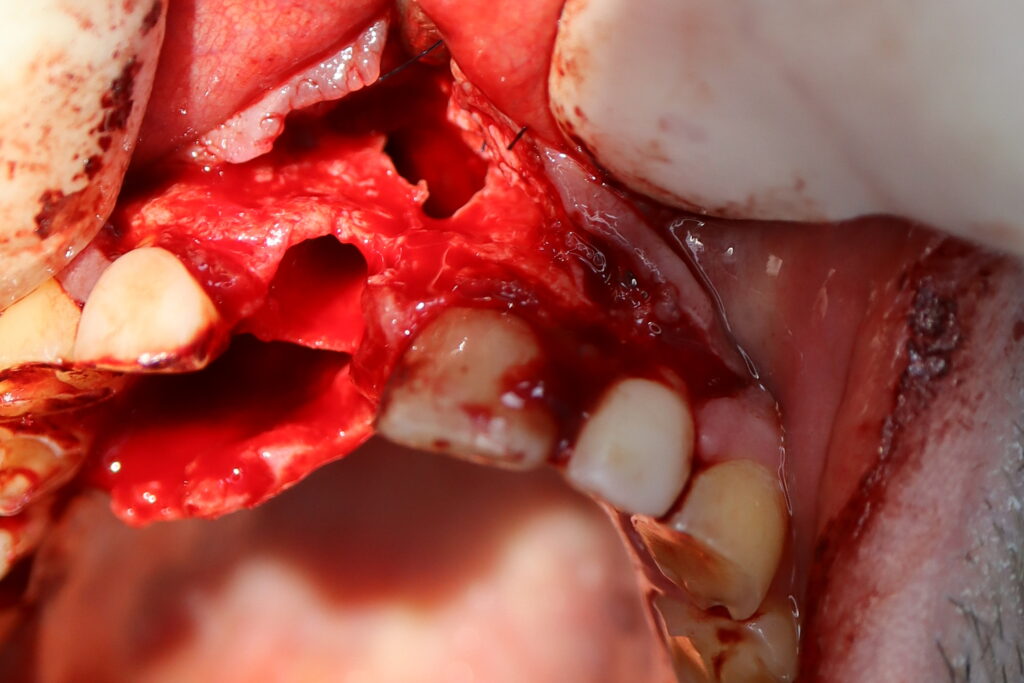

Процесс работы

Что было сделано:

Хирургом-имплантологом были проведены следующие манипуляции: удаление зуба 1.1, удаление кисты, аугментация твердых и мягких тканей в области 1.1

с применением свободного соединительнотканного трансплантата из слизистой оболочки бугра верхней челюсти, пластика уздечки верхней губы.

Установлен имплантат Straumann BLT и формирователь десны.

удаление зуба

Удаленный зуб и киста

Это фото может содержать тяжелый для восприятия контент